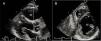

Measurement of epicardial adipose tissue thicknessAll included patients underwent detailed two-dimensional (2D), M-mode, Doppler, and tissue Doppler transthoracic echocardiography using standard techniques before beginning metformin monotherapy and after three months of treatment. The echocardiograms were performed by two experienced cardiologists who were blinded to the subjects’ clinical and demographic data. Each subject underwent 2D-guided M-mode transthoracic echocardiography using commercially available equipment (Aplio 500, Toshiba, Irvine, CA). Standard parasternal and apical views were obtained in left lateral decubitus position. EAT was visualized as echo-free space between the outer wall of the myocardium and the visceral layer of the pericardium (Figure 1). EAT thickness was measured perpendicularly on the free wall of the right ventricle during three cardiac cycles at end-diastole. Parasternal long- and short-axis views provided the most accurate measurement of EAT in the right ventricle, with optimal cursor beam orientation in each view. Maximum EAT thickness was measured at the point on the free wall of the right ventricle along the midline of the ultrasound beam perpendicular to the aortic annulus, used as an anatomic landmark for this view. For midventricular parasternal short-axis assessment, maximum EAT thickness was measured on the right ventricular free wall along the midline of the ultrasound beam, perpendicular to the ventricular septum at midchordal and tip of the papillary muscle level, as anatomic landmarks. The mean values from three cardiac cycles in each echocardiographic view were analyzed.

EAT thickness was significantly decreased after three months of metformin monotherapy (EAT0= 5.07±1.33 mm vs. EAT3=4.76±1.32 mm; p<0.001) (Figure 2).